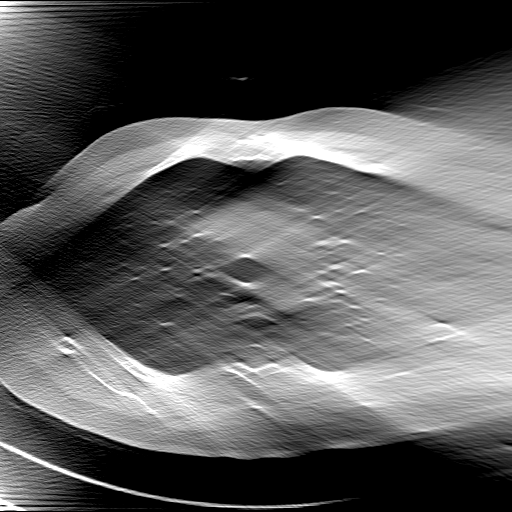

GT

FBP

HQS-CG

DuDoNet

Meta

Meta_re

EPNet

Qualitative Results Comparison. We also visualize the reconstruction results of these methods on AAPM-test and COVID-test datasets. As in the first three rows of Fig. 4, the reconstructed images from ours and retrained MetaInvNet show the best visualization quality on AAPM-test set across different angle numbers. Besides, our results show sharper details with the additional utilization of in the projection domain. When testing the reconstructed image on the COVID-test set, our result also gives sharper details but with more artifacts since the data distribution is very different. Although HQS-CG has achieved better quantitative results on the COVID-test dataset, the reconstructed image of their model in the fourth row is even smoother than FBP.